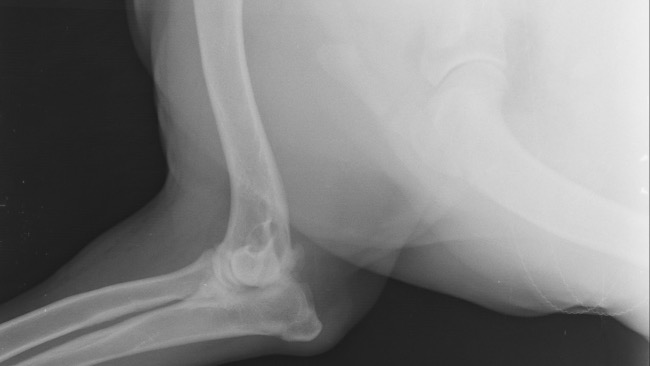

Chciałabym poinformować Was, ze z zebranych pieniążków zrobiliśmy jej tomograf komputerowy łapek. Specjalnie pojechaliśmy do Wrocławia, gdzie przyjmują najlepsi specjaliści. Diagnoza niestety nie jest najlepsza - musimy walczyć do końca.